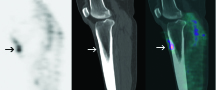

Radiolabelled White Blood Cell Study The image above demonstrates an accumulation of radiolabelled white blood cells indicating active infection.